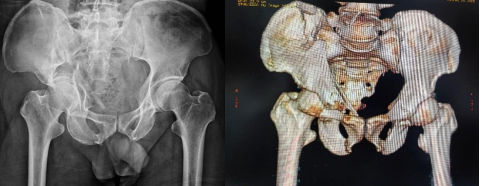

術(shù)后DR與CT顯示骨折復(fù)位固定好,關(guān)節(jié)面平整

手術(shù)期間,該院骨科團(tuán)隊(duì)按照術(shù)前規(guī)劃,精準(zhǔn)入路完成了良好的復(fù)位和固定,整個(gè)手術(shù)用時(shí)短,創(chuàng)傷小,出血量顯著減少,患者疼痛輕。術(shù)后復(fù)查顯示,關(guān)節(jié)面平整,頭臼關(guān)系匹配良好,且患者恢復(fù)迅速。